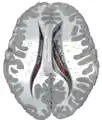

![]() Caudate nucleus (in red) shown within the brain | |

Transverse Cut of Brain (Horizontal Section), basal ganglia is blue | |

The caudate nuclei are located near the center of the brain, sitting astride the thalamus. There is a caudate nucleus within each hemisphere of the brain. Individually, they resemble a C-shape structure with a wider "head" (caput in Latin) at the front, tapering to a "body" (corpus) and a "tail" (cauda). Sometimes a part of the caudate nucleus is referred to as the "knee" (genu).[7] The caudate head receives its blood supply from the lenticulostriate artery while the tail of the caudate receives its blood supply from the anterior choroidal artery.[8]